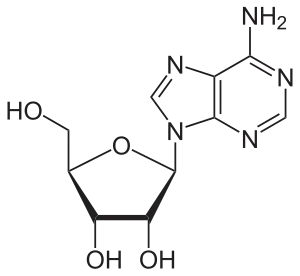

Adenosine consists of an adenine attached to a ribose via a β-N9-glycosidic bond.